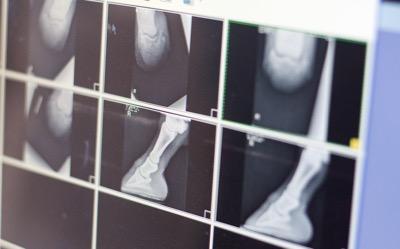

You can see how the DDFT attaches here. The tension creates movement of the coffin bone with damaged laminae.